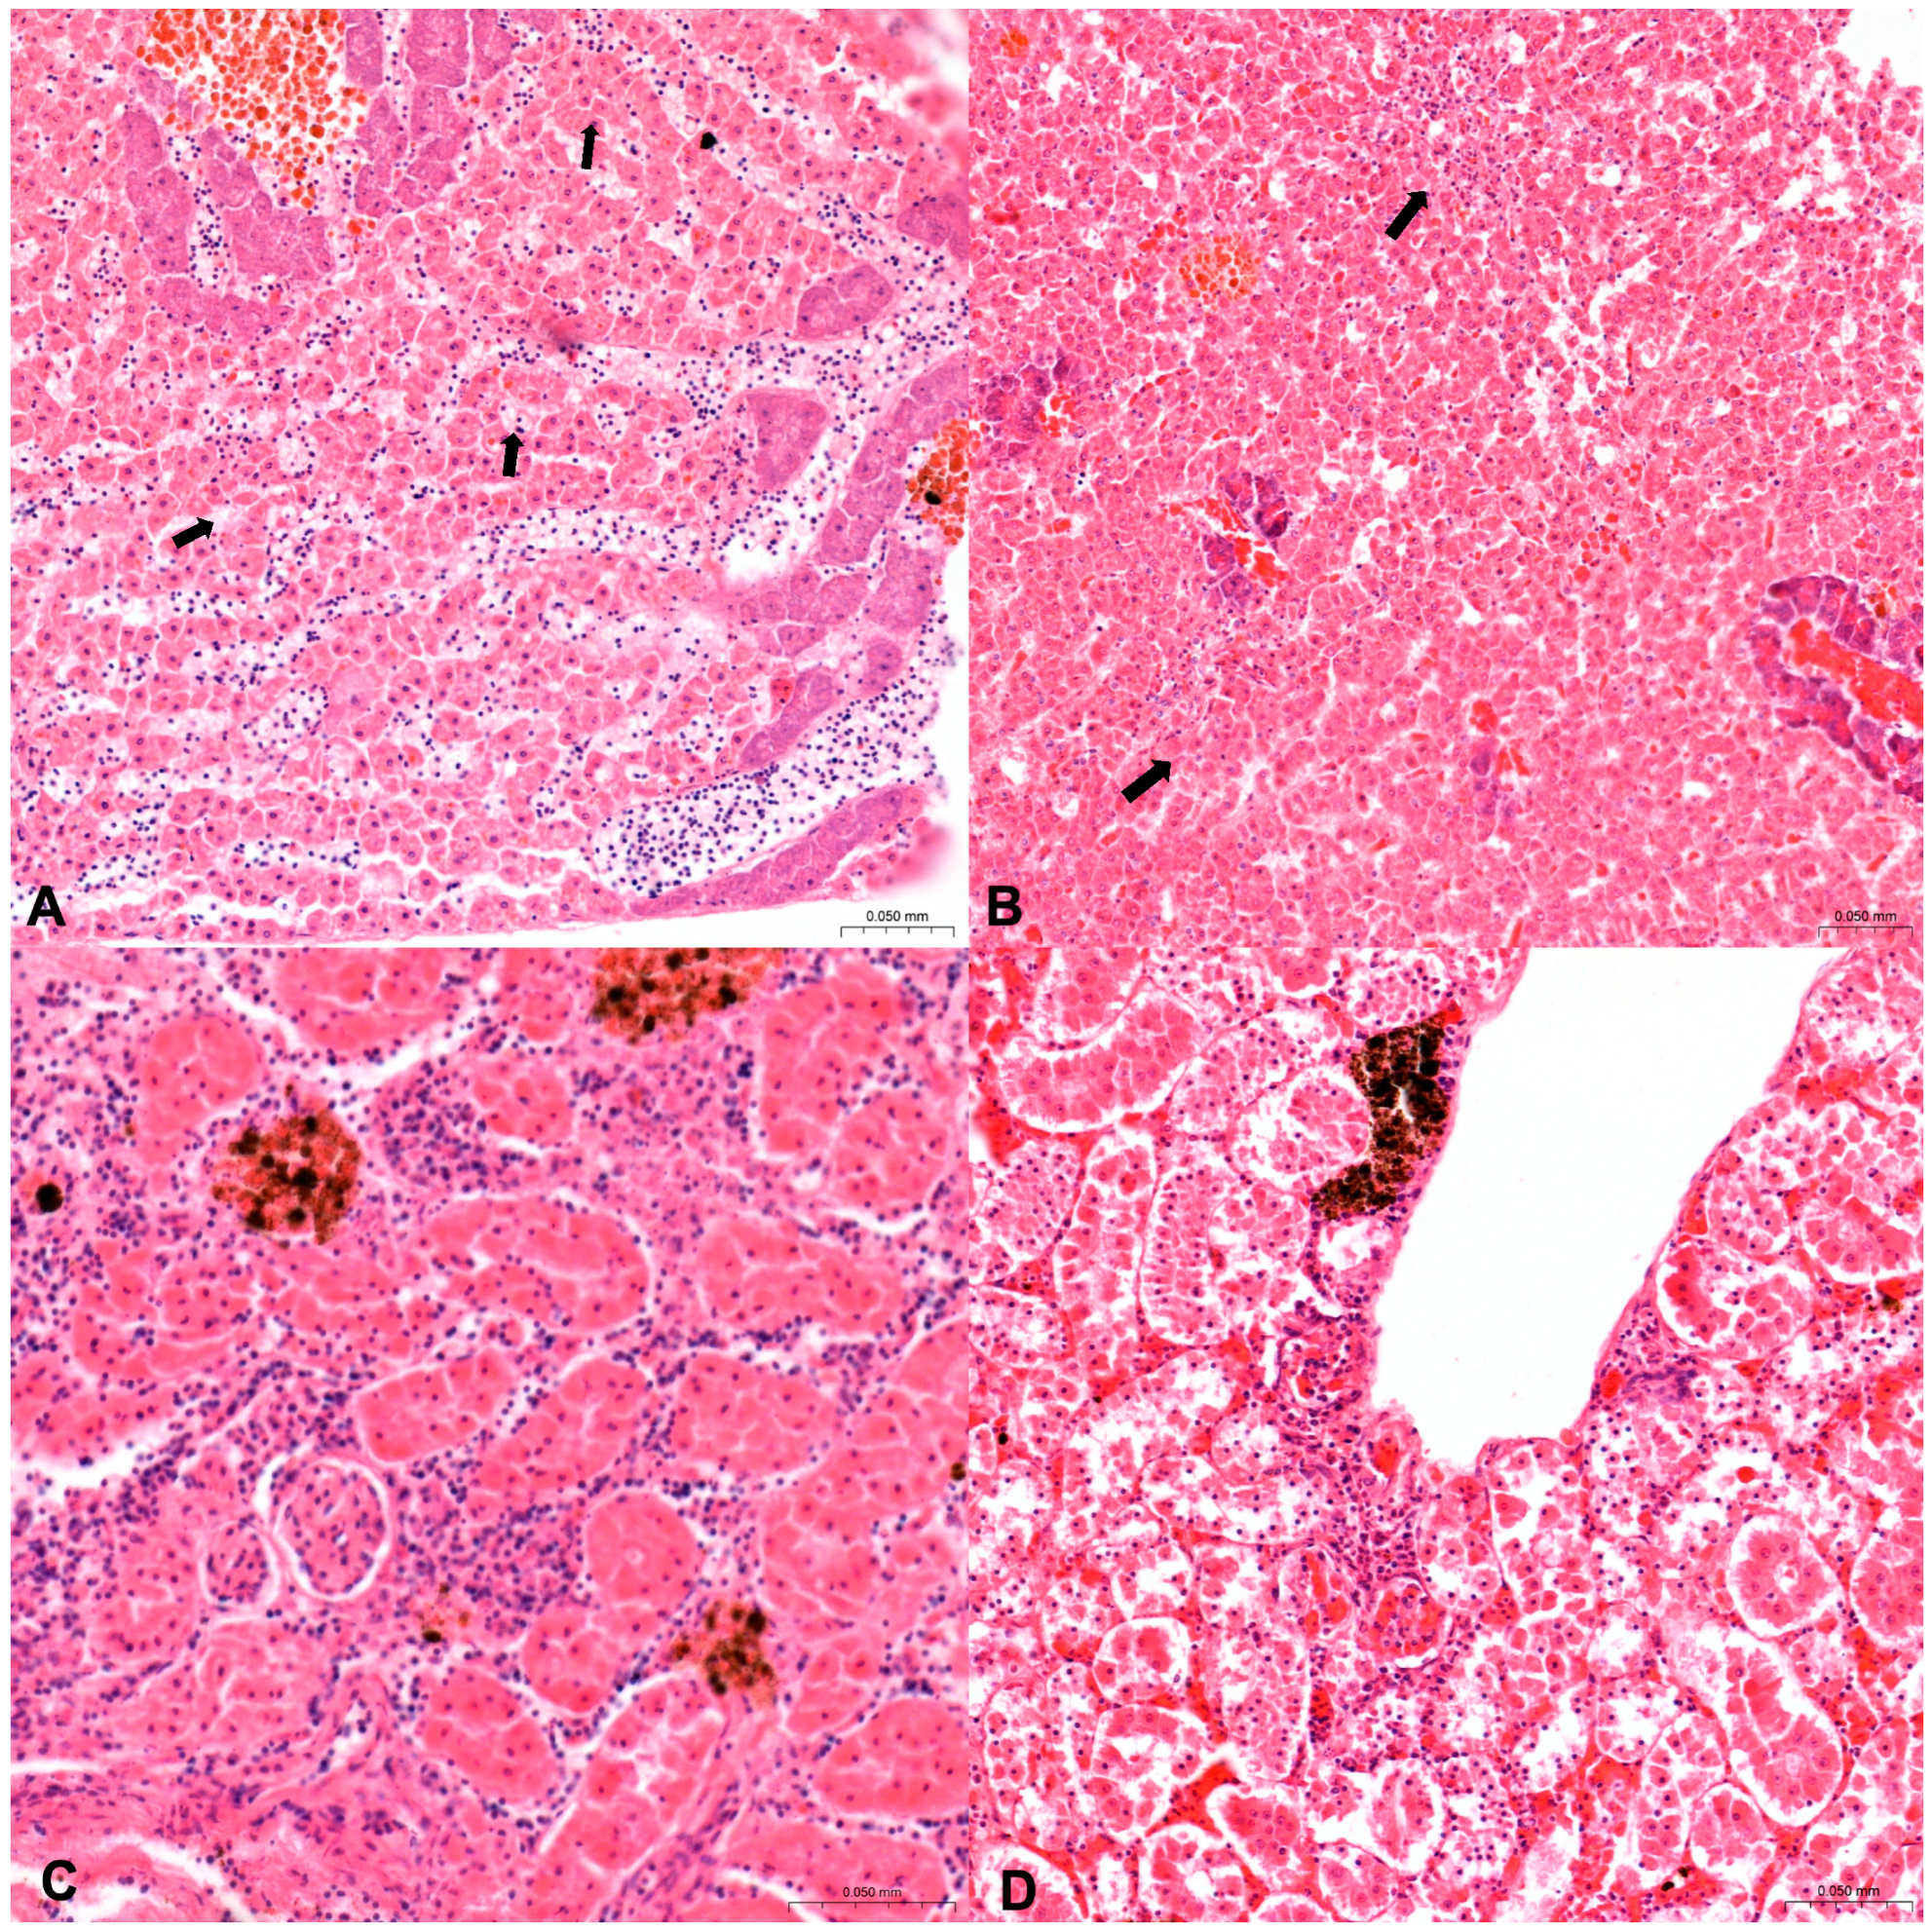

Figure 2.

Histological sections of hepatopancreas (A,B) in S. salpa from Sa and kidney in D. sargus from Sa (C,D) (hematoxylin and eosin, (10×)). (A) Normal hepatopancreas tissue with no increase in MMs (grade 0). (B) Hepatopancreas tissue with increase in number of MMs (grade 2), (black arrows). (C) Renal tissue with few MMs (grade 1) and (D) with substantial increase in MMs (grade 3), (black arrows).

Regarding the increase in number of MMs and MMCs (Figure 2) the results are summarized in Table 4. In Diplodus sargus from SA, 15% of both organs showed an increased number in MMs and MMcs. Among these, 7.5% (3/40) of both organs showed as grade 1, 5% (2/40) of both organs showed as grade 3, and 2.5% (1/40) of both organs showed as grade 2. In Diplodus sargus from Na, only 1.7% (1/60) of the hepatopancreas were grade 1, and 8.3% of kidneys resulting in an increase in number of MMs and MMCs were scored as follows: 3.3% (2/60) as grade 3; 3.3% (2/60) as grade 2; and 1.7% (1/60) as grade 1. In Sarpa salpa from Sa, 11.1% of hepatopancreas were considered with an increased number in MMS and MMCs and scored as follows: 6.7% (3/45) as grade 2; 2.2% (1/45) as grade 3; and 2.2% (1/45) as grade 1. Of kidneys with an increased number, 6.7% were scored as follows: 2.2% (1/45) as grade 1; 4.4% (2/45) as grade 2.

Histological evaluation of inflammation (Figure 3) in Diplodus sargus from Sa observed a total of 30% of hepatopancreas, scored as follows: 10% (4/40) as grade, 1.15% (6/40) as grade 2, and 5% (2/40) as grade 3. In kidneys, inflammation was observed in 22.5% and scored as follows: 7.5% (3/40) as grade 1 and 15% (6/40) as grade 2. In Diplodus sargus samples from Na, inflammation was observed in 18.3% of hepatopancreas, scored as follows: 10% (6/60) as grade 3, 6.7% (4/60) as grade 2, and 1.7% (1/60) as grade 1. In kidneys, inflammation was observed in 25% and scored as follows: 16.7% (10/60) as grade 2, 5% (3/60) as grade 3, 3.3% (2/60) as grade 1, and 10% (6/60) of livers as grade 3. In Sarpa salpa from Sa, inflammation was observed in 11.1% (5/45) of hepatopancreas, scored as grade 2, and in 2.2% (1/45) of kidney scored as grade 2. In Sarpa salpa from Na, inflammation was observed in 11.2% of hepatopancreas, scored as follows: 5.6% (3/54) as grade 2, 3.7% (2/54) as grade 1, and 1.9% (1/54) as grade 3. Inflammation in the kidney resulted in 53.7%, scored as follows: 37% (20/54) as grade 1, 12.9% (7/54) as grade 2, and 3.7% (2/54) as grade 3.